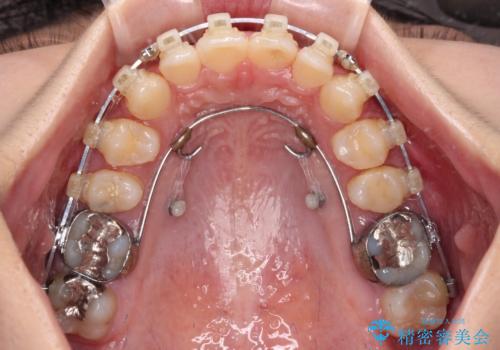

補助装置を用いて上顎大臼歯を後方に移動させながら、ワイヤー装置で歯列を整えて深い咬み合わせを挙上することとしました。

下顎の装置が頻繁に脱落し、治療は難航しましたが、当初予定の2年間で無事に治療を終えることができました。